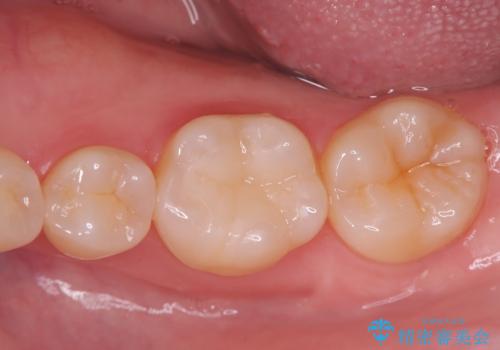

奥歯に虫歯があると言われた セラミッククラウンでキレイで長持ちする歯へ

担当医 榊原康平